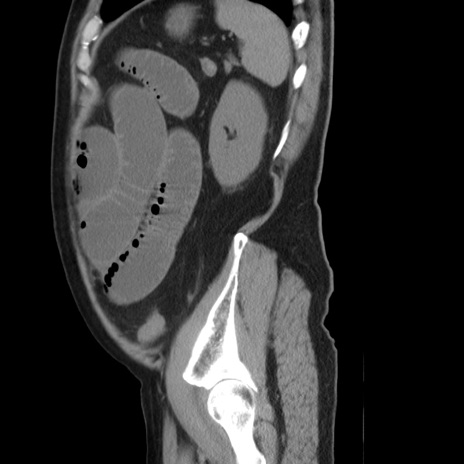

症例20(矢状断像)

【症例】 60歳代男性

【主訴】 腹部膨満、嘔吐

【現病歴】5日前頃より倦怠感を認め食事量減少し4日前の朝嘔吐、食事摂取困難となった。 3日前近医受診し点滴施行され整腸剤などを処方された。 当日他院を受診し、腹部膨満著明、炎症反応の上昇(CRP10.8、WBC11200)あり、紹介受診となる。

【身体所見】 意識JCS1 受け答えがはっきりしないBP 111/57mHg、 P 67bpm、、BT35.2°C、SpO2 97%(RA)、 腹部:膨隆、打診で鼓音あり、全体的に圧痛有り、腸蠕動音(-)、反跳痛ははっきりせず。

【データ】WBC 11400、CRP 14.20